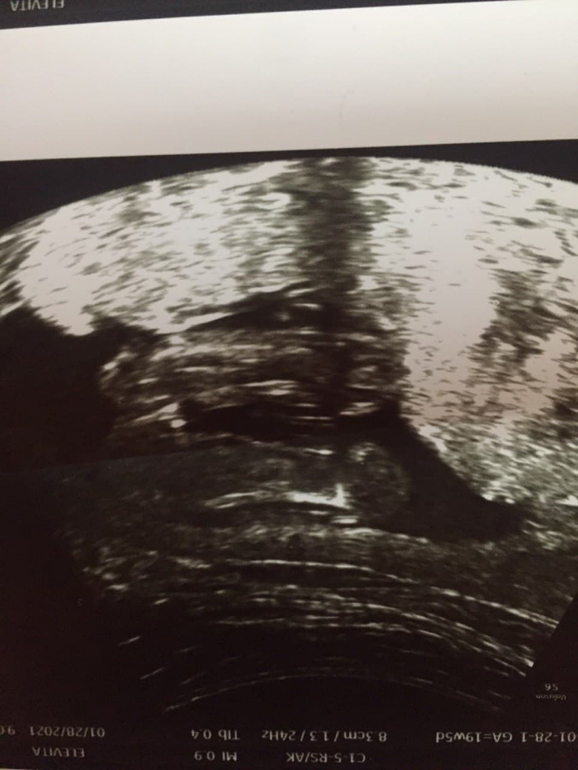

И ещё, что за аппарат УЗИ, нам в 17 недель показали чёткие причеткие бубенцы и писюн между ножками, хотя мы ещё в 10 недель сдали кровь из вены и знали пол